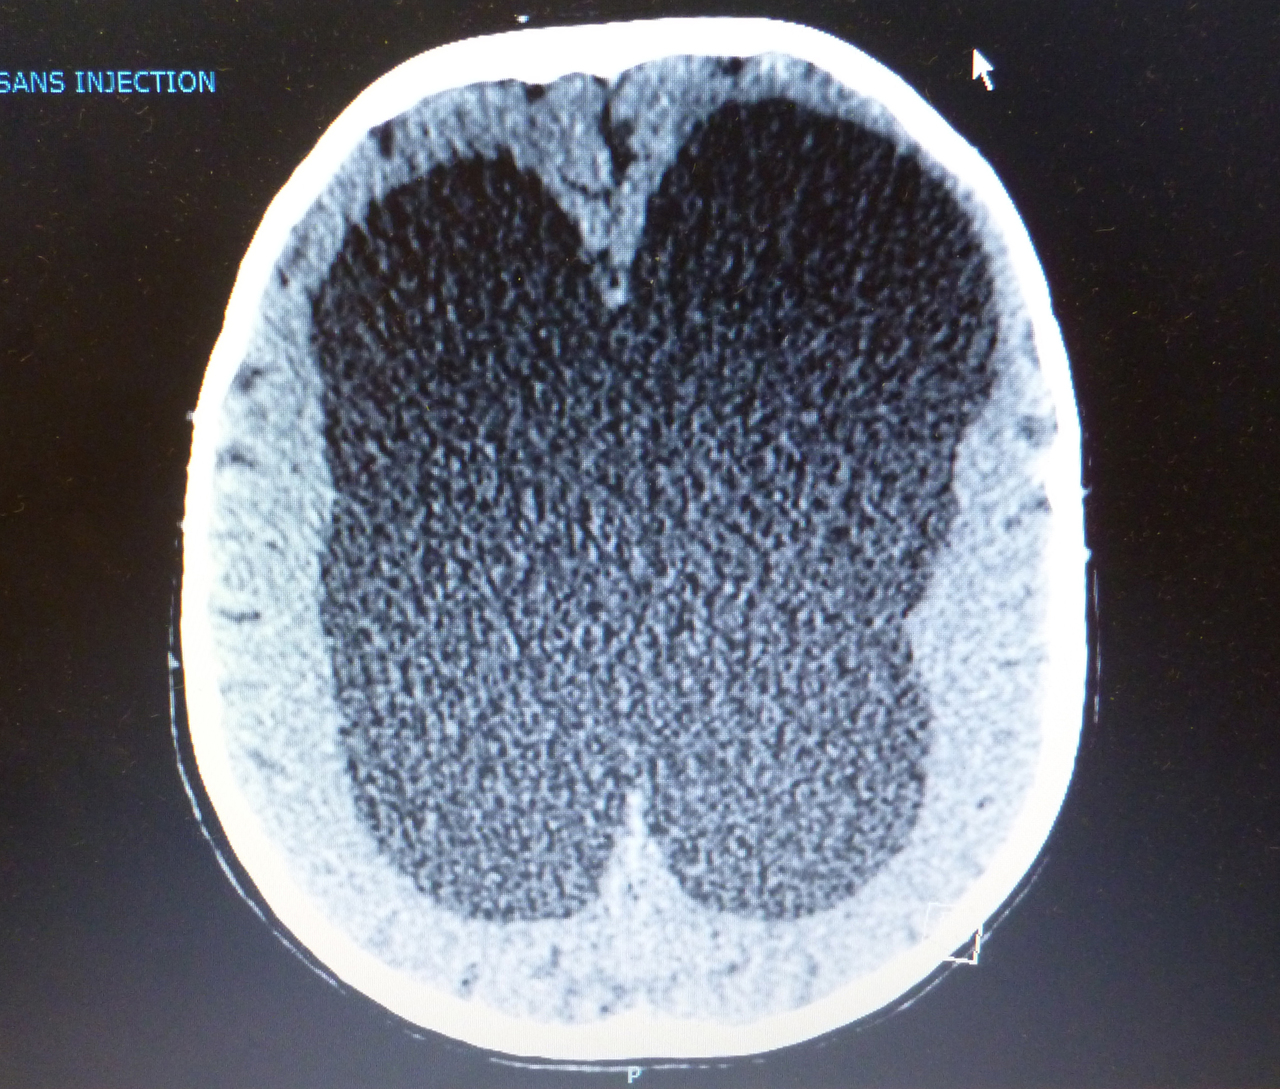

Quel est votre diagnostic ?

Il s'agit d'une hydrocéphalie par sténose de l'aqueduc de Sylvius.